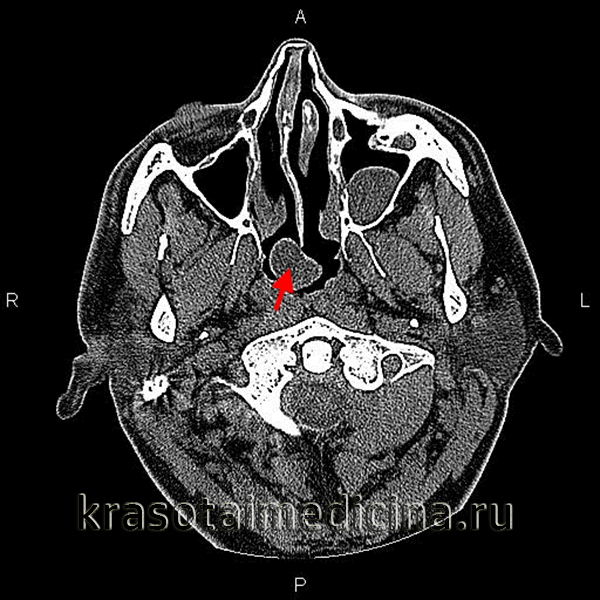

Заключение патогистологического исследования оболочки кисты: в срезах препарата оболочка кисты Торнвальдта, выстланная изнутри призматическими клетками (рис. 2). Элементы хронического воспалительного процесса.

Рис. 2. Оболочка кисты Торнвальдта. Внутренняя стенка выстлана призматическими клетками. Fig. 2. The e nvelope of Thornwaldt’s cyst. The inner wall is lined with prismatic cells.Окраска гематоксилином и эозином. Ув. 400. Staining with hematoxylin and eosin, x400.

Весь материал, удаленный интрао-перационно, подвергнут морфологическому анализу. Гистологическая картина подтвердила клинический диагноз.

- Биопсия. Гистологически слизистая оболочка внутри назофарингеальной сумки представляет собой цилиндрический мерцательный эпителий. Стенки полости в незначительной степени инфильтрированы лимфоцитами и содержат небольшое количество лимфоидных фолликулов.